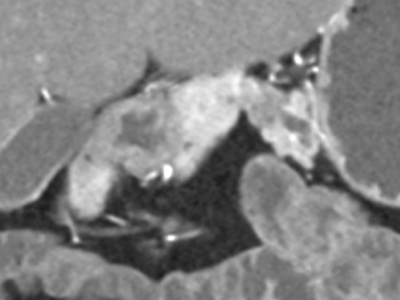

- What is the most likely diagnosis?

- Pancreatic ductal adenocarcinoma

- Chronic pancreatitis

- Autoimmune pancreatitis

- Normal

- Which of these statements about autoimmune pancreatitis is true?

- Normal serum IgG4 excludes diagnosis

- Diffuse hyperdense halo is typical

- Diffuse parenchymal calcifications are present

- Most patients respond to steroids